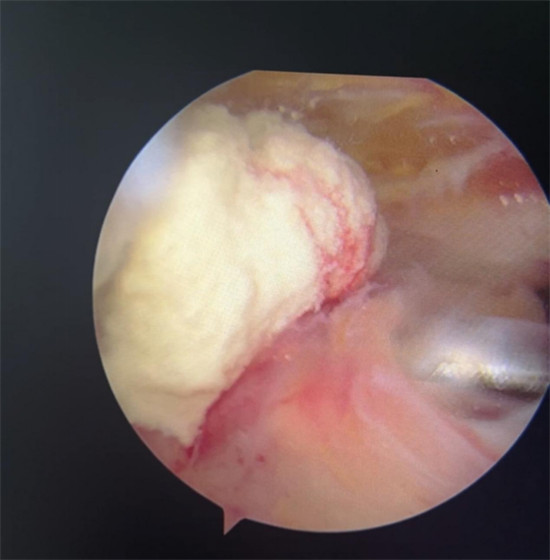

賀大媽慕名來廣安醫(yī)院找羅軍主任就診,面對羅醫(yī)生,賀大媽哭訴:“羅醫(yī)生,我真想剁下自己的這只胳膊。”羅軍主任根據(jù)患者的癥狀拍片,診斷為岡上肌鈣化性肌腱炎,隨后,羅醫(yī)生為李大媽進(jìn)行了肩關(guān)節(jié)鏡微創(chuàng)手術(shù),竟從她的右肩“擠”出“牙膏”。

鈣化性肌腱炎是一種自限性疾病,就是疾病發(fā)生發(fā)展到一定程度后,經(jīng)長期機體調(diào)節(jié)能夠控制病情發(fā)展并逐漸恢復(fù)痊愈。它分為四個階段:鈣化前期、鈣化形成期、鈣化吸收期、鈣化后期,往往在“鈣鹽斑塊”吸收時,疼痛最劇烈,賀大媽就正處于“吸收期”。

羅軍主任表示,很多人會把肩痛都?xì)w因于肩周炎,這是一個很大的誤區(qū)。其實,肩痛人群中只有15%左右是肩周炎,大部分肩膀疼痛由于肩袖損傷、肩峰撞擊征、鈣化性肌腱炎。而大多數(shù)人也因此認(rèn)為忍一忍就會自愈,常常延誤治療,關(guān)節(jié)鏡微創(chuàng)治療鈣化性肌腱炎,可以快速緩解疼痛,同時可以修復(fù)肩袖損傷,清理肩膀骨刺。